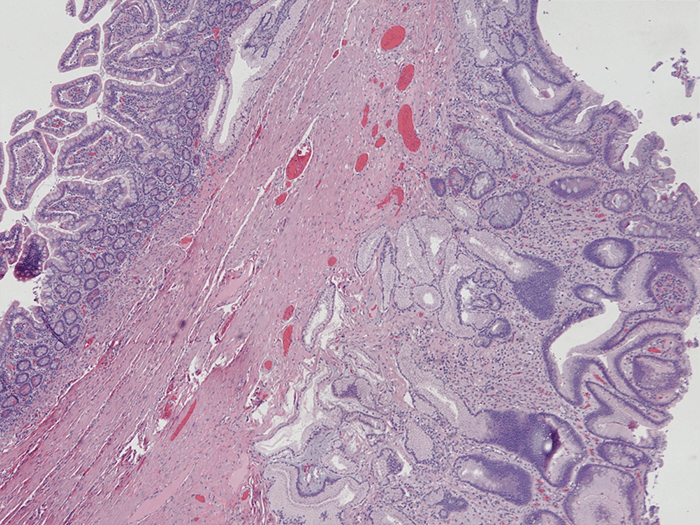

A 28-year-old female with a past medical history of intestinal tuberculosis (TB) and chronic constipation presents with worsening constipation for one year. In 2009 she was diagnosed with tuberculosis based on symptoms of fevers, chills, nausea, and chronic abdominal pain. She was treated with isoniazid, pyrazinamide and ethambutol for approximately 1 year, her imaging at the time of diagnosis was negative for pulmonary disease, but positive for multiple intestinal strictures. After completion of therapy, she had improvement in her strictures on imaging, but continued to have intermittent episodes of severe abdominal pain, bloating, anorexia, nausea, and constipation if any significant amount of fiber was ingested. This was managed on a low residue diet and daily lactulose for about 10 years. In 2018 she presented to our clinic. A computed tomography (CT) scan was obtained (Figure 1) demonstrating a transition point in the mid jejunum with dilation of her small intestine proximally. She was taken to the operating room, where she was found to have a single mid-jejunal stricture with two proximal scybala creating a ball-valve mechanism (Figure 2). She received a segmental resection, primary anastomosis and biopsy of mesenteric lymph node. The specimens were sent for pathology and culture, which were negative for tuberculosis. H&E staining of the resected specimen demonstrated gastric heterotopia with antral type mucosa devoid of other gastric mucosal subtypes (Figure 3). Mesenteric lymph nodes were without active TB and showed reactive follicular hyperplasia without granulomas, consistent with a prior TB infection. QuantiFERON gold test was positive, but a chest x-ray was negative for active TB.

Figure 4. Histology of Resected Small Bowel with Gastric Heterotopia. Normal small bowel mucosa (left) and heterotopic gastric antral type mucosa (right). Hematoxylin & Eosin (H&E) stain, 40x magnification.

Gastric heterotopia is relatively common finding in the duodenum and proximal jejunum, but somewhat rare in the jejunum.68 Gastric heterotopia can be divided into at least two subtypes: congenital and metaplastic. These are differentiated by the presence of multiple histologic subtypes of gastric mucosa, which indicates a congenital origin, versus only antral or pyloric mucosa in metaplastic gastric heterotopia. Meckel's diverticulum is an exception to that rule, as it is a congenital cause but usually contains only antral or pyloric mucosa.68 It is thought that metaplastic heterotopia occurs in response to insult and has been seen in conditions such as regional enteritis, tuberculous enteritis, surgical anastomosis, malignancy, radiation and inflammatory bowel disease.9 Lee's paper9 is of particular relevance as he describes six patients who had verified tuberculosis affecting the small bowel, all of whom were females, who had pyloric metaplasia associated with "inflamed or ulcerated mucosa overlying the tuberculous lesion or in the more proximal, obstructed parts of the bowel." Thus, with the known clinical course of our patient and the histology of her stricture, we believe that her stricture was a residual sequalae of intestinal TB.